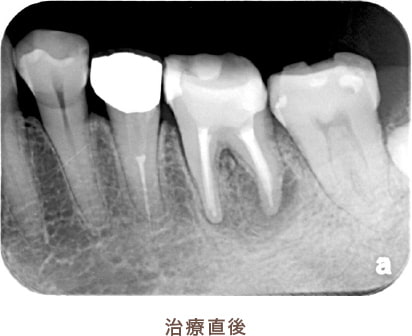

外すと中がドロドロに虫歯に感染していました。

折れて残っていた機具を除去

根管の中を洗浄し、無菌に近い空の状態にした。

根管の中を封鎖し終了。

治療後病気がなくなり骨が再生した